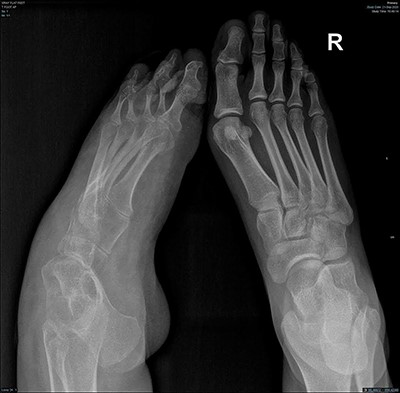

Magnetic resonance imaging (MRI) brain and whole spine were ordered for her due to the neurological pattern of the disease. The MRI showed T4–T5 posterior fusion, there were no other neurological lesions. For evaluation of the varicose veins, vascular consultation was obtained, and Doppler ultrasound was ordered, which showed absent popliteal deep veins. Radiography of the left foot revealed marked cavus as well as hindfoot and forefoot varus. Also, it showed soft tissue swelling, reduction in bone density, and no evidence of fracture or dislocation or tarsal coalition (Fig. 2). The right foot radiograph was unremarkable apart from mild hallux valgus deformity (Fig. 3).

AP radiograph of both feet showing cavovarus deformity of left foot and right hallux valgus.